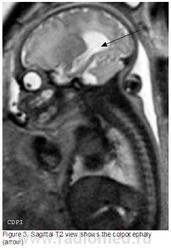

3. и 4. На саг. Т2 колпоцефалия (стрелка)

6. На Саг. Т2 колпоцефалия (стрелки)